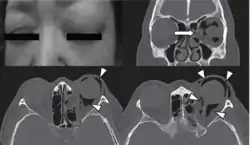

Woman with preorbital swelling in orbital emphysema shown in CT scans